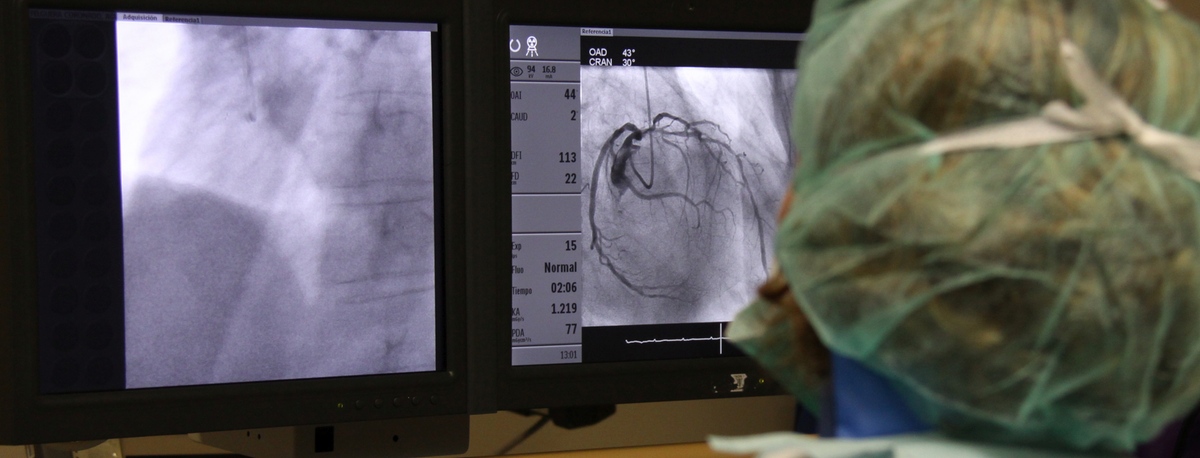

Instituto del Corazón Quirónsalud Teknon

A l'institut comptem amb especialistes en angiologia, cirurgia vascular i endovascular per al diagnòstic i seguiment de les malalties de l'aparell circulatori. L'embòlia cerebral i el tromboembolisme pulmonar són algunes de les causes principals de mort deguda a un problema vascular.

El nostre equip és especialista en tècniques mínimament invasives, utilitzant tècniques endovasculars, sense cirurgia, que permeten implantar pròtesis vasculars per resoldre dilatacions o aneurismes de les artèries. També oferim tots els tractaments de la patologia venosa i arterial perifèrica, incloent-hi les malalties de les artèries caròtides.